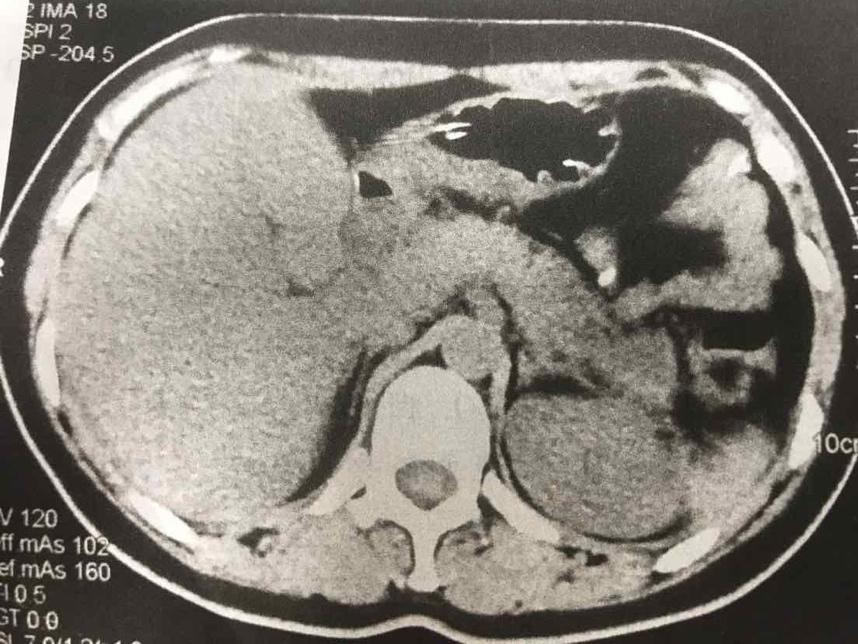

摘要:本文介紹了急性胰腺炎的最新分型,包括其分類標(biāo)準(zhǔn)和特點(diǎn)。文章還提到了一天的奇妙之處與急性胰腺炎分型之間的聯(lián)系,強(qiáng)調(diào)了及時(shí)診斷和治療的重要性。全文旨在提高人們對(duì)急性胰腺炎的認(rèn)識(shí),以便更好地預(yù)防和治療該疾病。